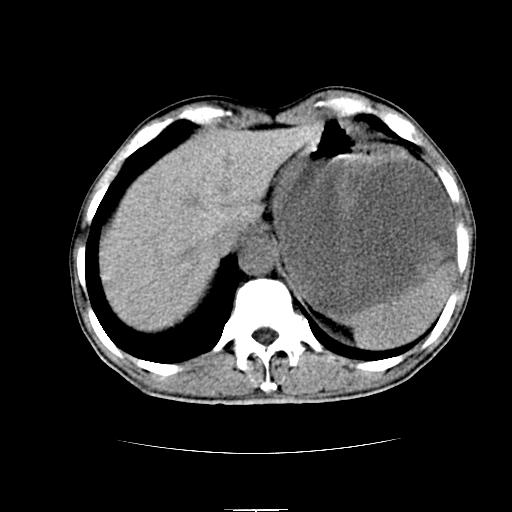

标题: CT6969:腹部,某男 34岁,腹痛治疗半月无效 [打印本页]

标题: CT6969:腹部,某男 34岁,腹痛治疗半月无效

左上腹胃、脾及胰腺间巨大囊性占位性病变,内见多数薄隔,有轻度强化,明显占位效应。左肾见一小囊肿。

考虑:1、左上腹巨大囊肿(可能来源于胰腺)。

2、左肾小囊肿。

左上腹胃、脾及胰腺间巨大囊性占位性病变,内见多数薄隔,有轻度强化,明显占位效应,胰腺及左肾结构清楚,明显向后下方推压 移位。左肾见一小囊肿.多考虑:1 网膜巨大囊肿。2 左肾小囊肿。

1胃脾胰之间一巨大囊性影,胃明显向前推移,胰体尾部似肥大,考虑囊性影来源于胰腺(假性囊肿?)2左肾小囊肿。

胃脾胰之间一巨大囊性影,内可见间隔,应为囊实性占位:多考虑:1 网膜巨囊腺瘤?。2 左肾小囊肿

左上腹胃、脾及胰腺间巨大囊性占位性病变,其内见多数薄隔,有轻度强化,明显占位效应。左肾见一小囊性变。

左肾囊肿;网膜巨大囊肿。